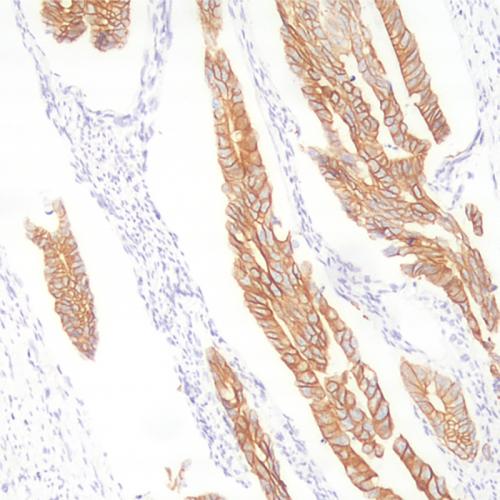

產(chǎn)品特點(diǎn):EB病毒(Epstein-Barr virus,EBV)由布里斯托大學(xué)名譽(yù)教授Michael Anthony Epstein和倫敦大學(xué)的Yvonne Barr共同發(fā)現(xiàn)和命名。EBV是一種普遍存在的人類皰疹病毒,90%以上的健康成人攜帶該病毒。EBV感染與許多腫瘤的發(fā)生相關(guān),如Burkitt淋巴瘤、霍奇金淋巴瘤和鼻咽癌等,國(guó)際癌癥研究署(IARC)將EBV列為致癌因子。EBERs(EBV-encoded RNAs)大量存在于EBV潛伏感染的細(xì)胞中,每個(gè)細(xì)胞可達(dá)106~107拷貝,是EBV潛伏感染的可靠標(biāo)志物。EBER原位雜交是檢測(cè)組織和細(xì)胞中EBV的標(biāo)準(zhǔn)方法。本試劑盒使用的EBER探針是地高辛標(biāo)記的核酸探針,具有很高的特異性和敏感性。